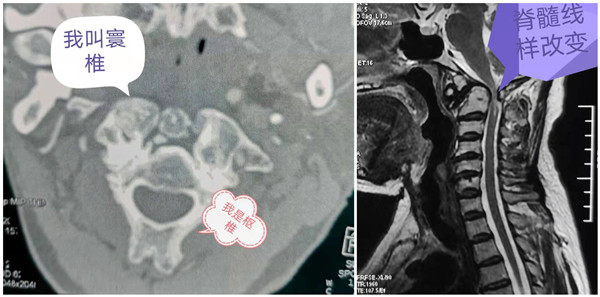

患者何某某,女,以“四肢麻木无力4年,加重2月”之主诉于元旦前夕入院。4年前出现行走不稳,1年前出现双手无力,握持不灵活。就诊于外院住院检查示“寰枢椎脱位”,因患者病情重,且寰枢椎手术复杂,当地医生介绍至我院臧全金教授处治疗。臧教授接诊后查体发现患者行走困难,需外人搀扶方能行走。通过影像检查发现患者寰枢椎脱位明显,原先上下关系的寰枢椎脱位成为前后关系,且寰枢骨质增生严重;椎管处狭窄,脊髓受压变成线状。此例患者为类风湿性关节炎侵犯寰枢椎所致,且因为病程长,寰枢椎脱位严重,难以通过简单的牵引达到复位。臧教授及治疗小组同患者和家属详细解释病情及治疗方案等具体事项,制定了完备的手术计划。在元旦假期间,组内联系手术室,积极准备手术用品,臧教授根据病情及治疗需要,个人也准备了一些相关器械,以保障手术顺利进行。